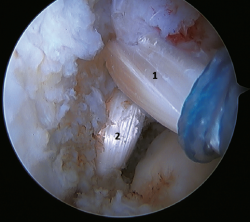

A recent consensus(64) recommends reconstruction of the ATFL and CFL (Figures 5 and 6) in cases of generalized laxity or when there is poor tissue quality. Other indications would be when there are doubts about subtalar stability or in patients with a ruptured CFL. For some authors, BMI > 30 kg/m2 would also be an indication for this technique.

Figure 6. Arthroscopic view of a dual allograft reconstruction of the anterior talofibular ligament (1) and the calcaneofibular ligament (2), showing correct tension and positioning of the fascicles.